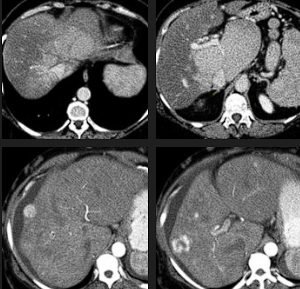

Esteatose hepática difusa associada à quimioterapia em paciente com metástases hepáticas de câncer colorretal.

A quimioterapia é um fator de indução da DHGNA.